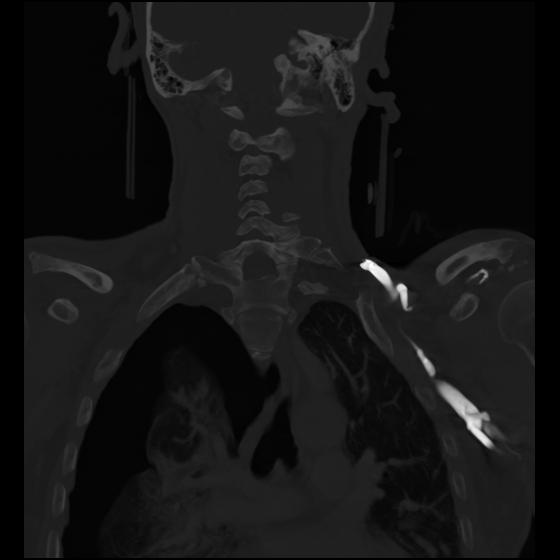

23 ANGIO,CE,Cor-MIP,5.000,ANGIO,Cor-MIP,